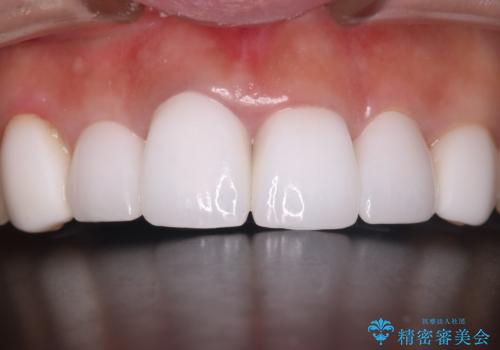

- 他院で治療した前歯の色が気になるということで来院された患者様です。前歯に色の差があり、レントゲンから内部にう蝕も見られたため、審美性に優れ、う蝕になりにくいオールセラミッククラウンで治療いたしました。

清掃性も上がったおかげで、歯肉の状態も良好に保てています。

色の調和もとれたので非常に満足いただけました。